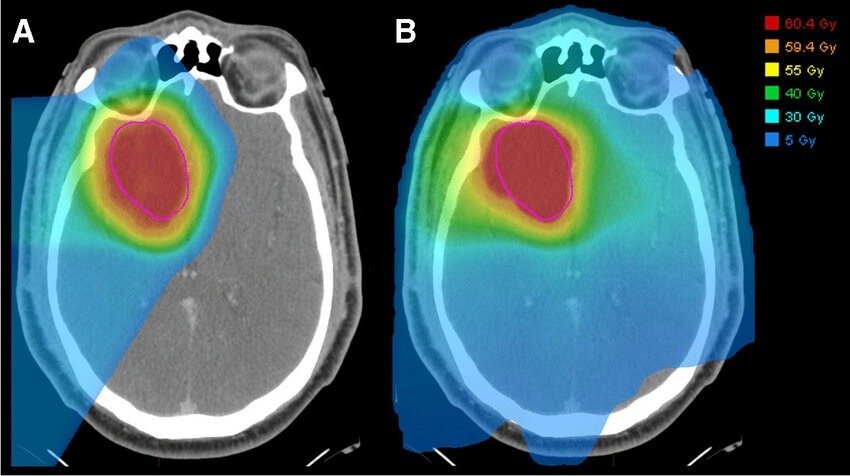

• Όγκοι κεφαλής–τραχήλου, ειδικά όταν απαιτείται πολύ προσεκτική προστασία σιελογόνων, οπτικών δομών και εγκεφαλικών περιοχών (Photo 2).

Όγκοι Κεφαλής-Τραχήλου

Photo 3